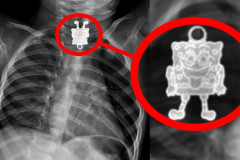

10 տարօրինակ իր, որ հայտնաբերվել են մարդկային մարմնում (տեսանյութ)